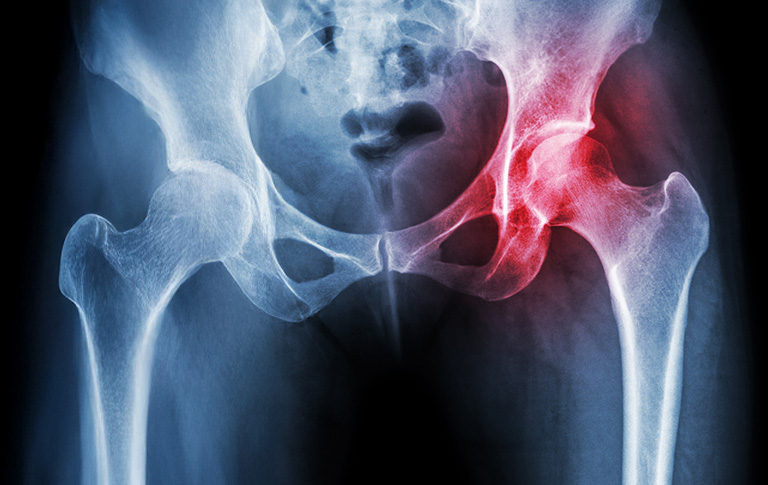

Anterior hip replacement is a minimally invasive surgical approach that accesses the hip joint from the front, significantly reducing muscle disruption and enhancing early recovery.

Anterior hip replacement involves replacing the damaged hip joint through an anterior (front) incision, minimising muscle trauma and enhancing postoperative outcomes.

Posterior hip replacement involves accessing the hip joint from the side or back, a traditionally effective method suitable for a variety of patient conditions.

The posterior approach accesses the hip joint through an incision from the side or back, a traditional and proven, reliable method for diverse surgical requirements.

Ideal candidates for anterior or posterior hip replacement experience significant hip pain, limited mobility, or dysfunction due to conditions such as osteoarthritis, rheumatoid arthritis, or other degenerative joint diseases that haven’t adequately responded to non-surgical treatments.